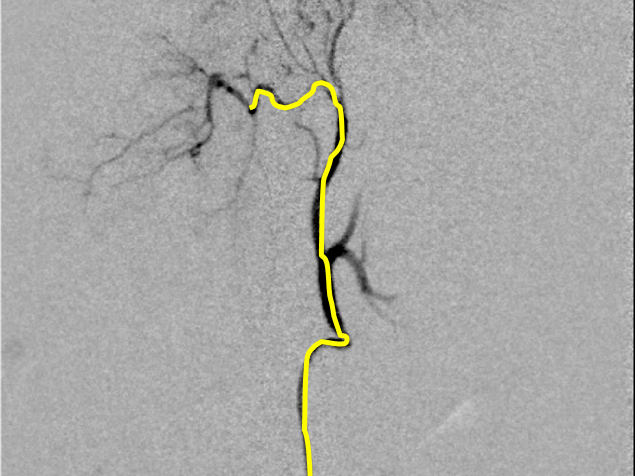

【実施症例】腰下リンパ節に転移した血管肉腫に対する動注療法

腰下リンパ節に転移した血管肉腫。

腫瘍の頭側の腹大動脈にリザーバーを設置し、抗がん剤の投与を行った。腫瘍は1/3以下に縮小が認められた。

血管肉腫が転移した腰下リンパ節

腫瘍陰影(DSA画像)